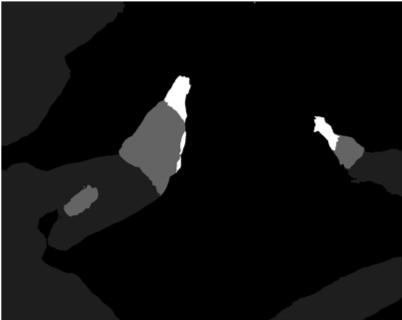

Our challenge was made up of 3 sub-problems. The first was binary instrument segmentation, where each frame was separated into da Vinci Xi instruments and a background class, which contained an ultrasound probe, surgical clips and porcine tissues. The second task was instrument part segmentation, where we scored the participants on whether they could correctly segment each articulating part of the instrument (see Fig. 3). Our final task was to segment and classify the instruments (see Fig. 4).

Our labelling was performed by a dedicated segmentation team at Intuitive Surgical using the open source software Viame333https://github.com/Kitware/VIAME which provides functionality for frame-by-frame polygon creation. We labelled only the left eye in the stereo pair to reduce labelling time. Labels were provided on an instance level with separate annotated images per object.